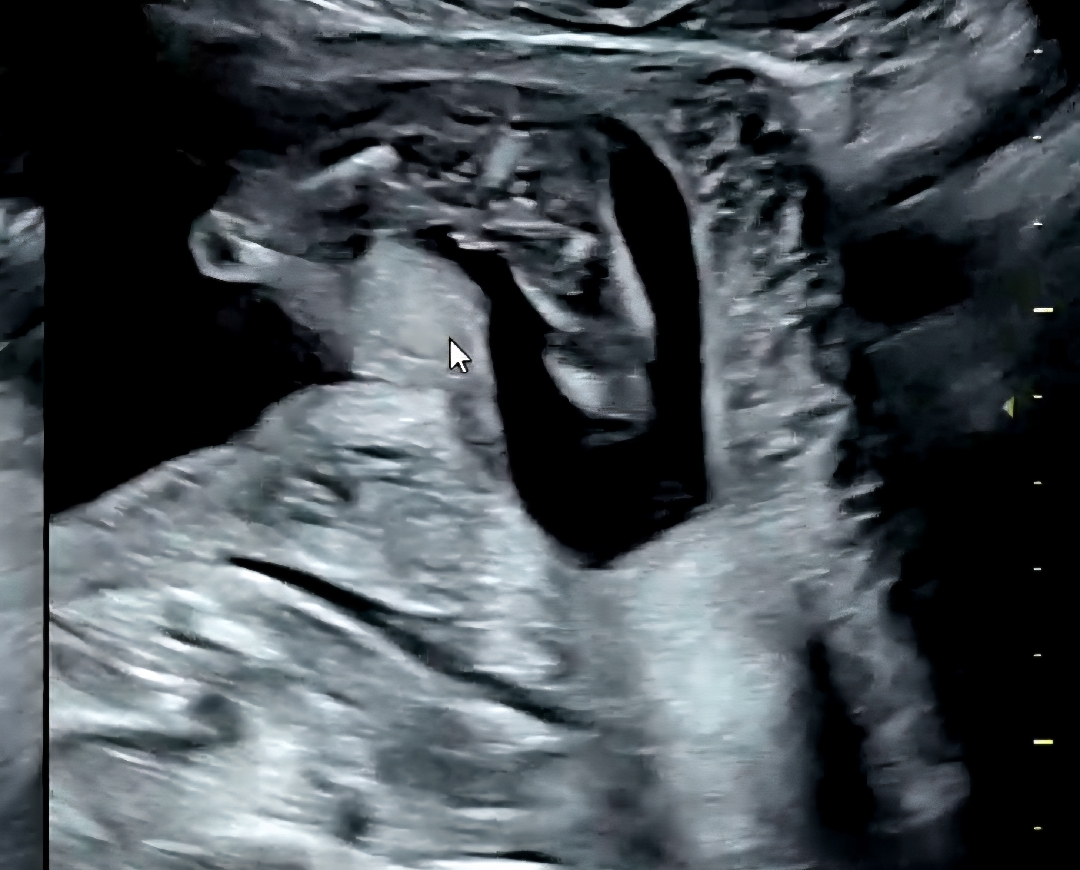

16주 1일 성별알려주세용

16주 1일인데 딸인가용 아들인가용

딸이요! 셋째넷쩨 딸인데 딱 저랬어요 아들은 ㅋㅋ 안저래요

딸같아여 ㅎㅎ